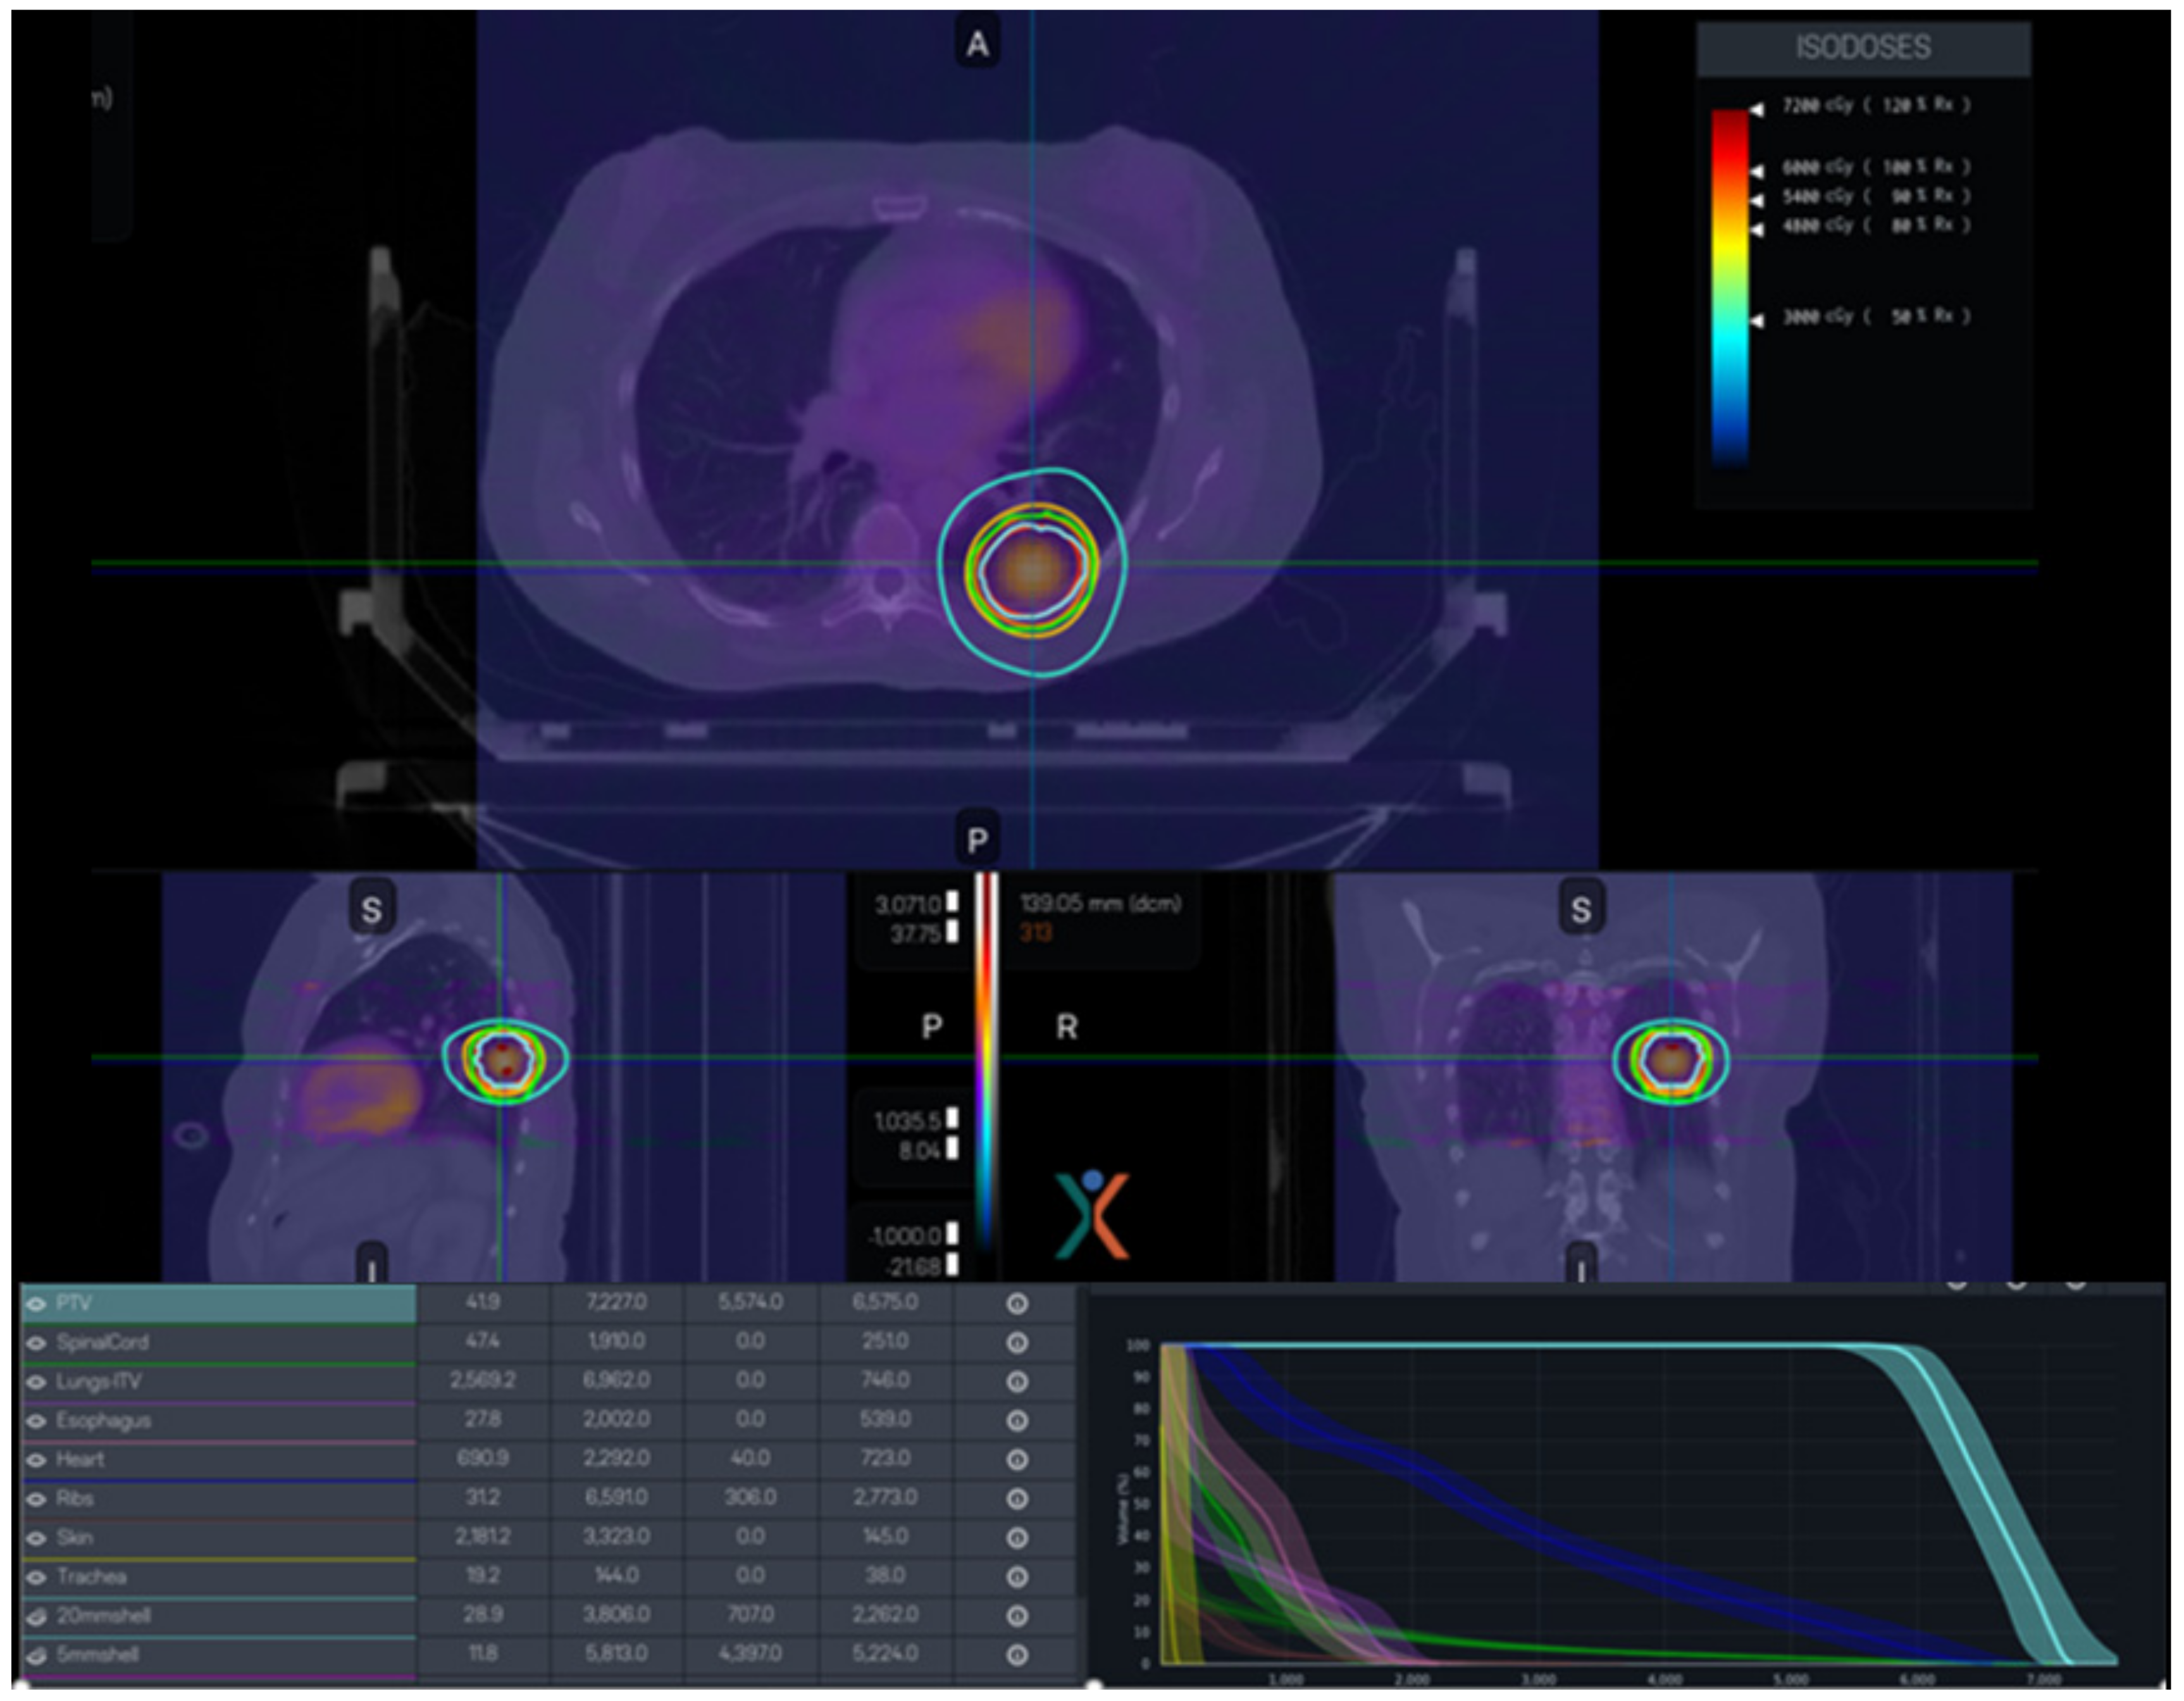

4.3. PET-Based ART

5.2. Lung Cancer